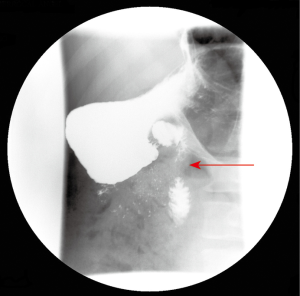

A 46-year-old Caucasian male with a smoking index of 30 pack-years and chronic alcohol consumption of 160 grams per day, with no history of past medical conditions, and with a family history of pancreatic and gastric cancer, presented to the emergency unit with a 6-month history of intermittent colicky epigastric pain irradiated to both hypochondria and back, with a progressive increase in intensity that worsened with food intake causing a limitation to food ingestion that lead to asthenia and loss of 20 kg. of weight in the previous 6 months. He also described post-prandial fullness, nausea and a change in bowel habits for the last 5 months in the form of progressive constipation for which he underwent colonoscopy 3 months prior to his presentation that only revealed a sessile polyp in the descending colon without histological abnormalities. He denied vomiting, hematemesis, hematochezia or melena. On examination he was normotensive, afebrile, with normal rubor. Abdominal examination revealed tenderness in epigastrium and both hypochondria with abdominal guarding, and normal bowel sounds. No masses were palpated. Proton pump inhibitors, gastroprokinetic agents and analgesia with acetaminophen and metamizole didn’t alleviate his symptoms. Laboratory tests revealed normal leukocyte count, acute phase reactants, liver and pancreatic enzymes. Abdominal X-ray showed no abnormalities, and he was admitted to hospital for further study, undergoing upper gastrointestinal endoscopy that revealed grade I oesophageal varices, mild hiatal hernia and chronic antral gastropathy. Abdominal ultrasonography revealed a small hepatic hemangioma with homogenous hepatic parenchyma, and no biliary, pancreatic or splenic anomalies. After progression of the severity of symptoms further study was followed with computerized tomographic enterography that revealed a band of pancreatic parenchyma surrounding the descending portion of the duodenum, with the pancreatic duct opening in the duodenum anterior and superior to the biliary duct opening (Figure 1). Barium meal was done that revealed an extrinsic compressing effect on the descending part of the duodenum without obstruction, proximal dilatation or gastric retention (Figure 2). Conservative treatment with analgesics, soft diet, proton pump inhibitors and gastroprokinetic agents was decided at first considering that the patient didn’t show duodenal obstruction or any other complication, with failure to control the symptoms. Due to failure of conservative treatment and high risk of the patient to develop complications (chronic smoker and heavy alcohol consumer, family history) surgical approach was decided. Laparoscopic duodenojejunostomy was performed with no post-operative complications. No enlarged lymph nodes were detected in the periportal or peripancreatic regions. Relief of symptoms was achieved after 48 hours of the procedure. The patient had an improved appetite with progressive gain of weight in the following year of follow-up.